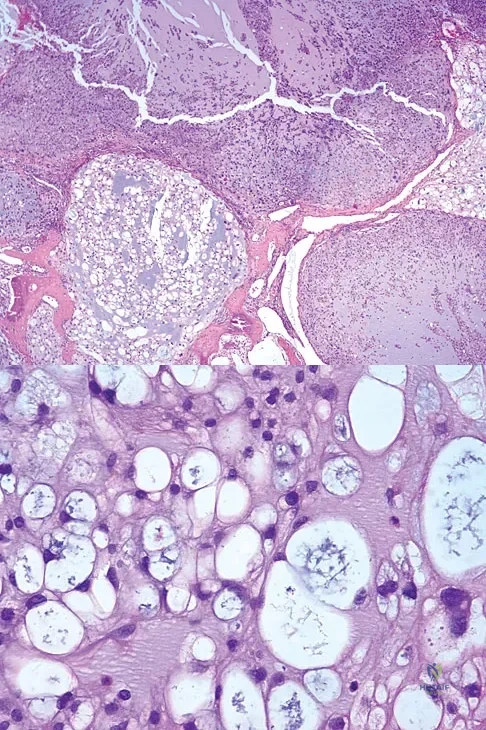

A 73-year-old man stepped off a street curb and felt a crack in his left hip. He is now unable to bear weight. A radiograph is shown in Figure 54a. Biopsy specimens are shown in Figures 54b and 54c. What is the most likely diagnosis?

Explanation